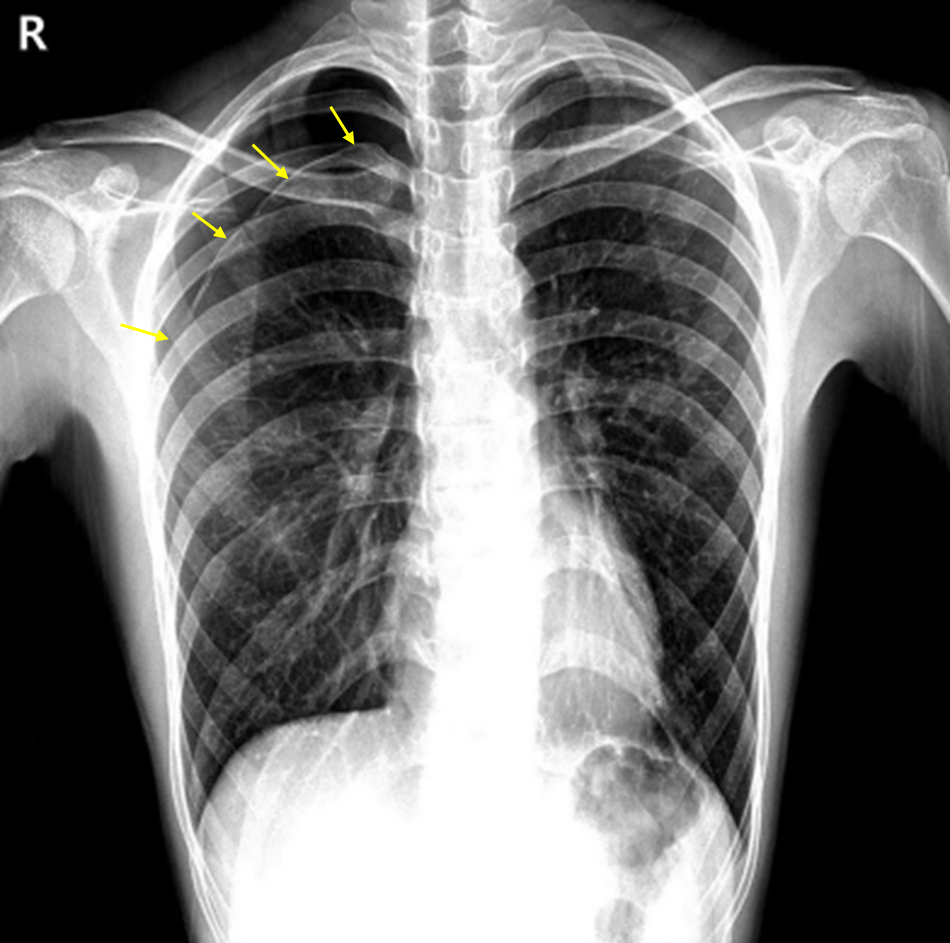

19세 남자가 2시간 전부터 갑자기 오른쪽 가슴이 아파서 병원에 왔다. 숨을 들이마실 때 통증이 더 심하다고 한다. 특별한 과거력은 없으며, 키 185 cm, 체중 55 kg이다. 혈압 120/80 mmHg, 맥박 90회/분, 호흡 24회/분, 체온 36.7℃이다. 가슴청진에서 오른쪽 폐에서 호흡음이 감소되어 들린다. 혈액 검사 결과는 다음과 같다. 가슴 X선사진이다. 진단은?

Img | CXR: Rt. pneumothorax |

CXR상 visceral pleural line 및 distal pulmonary vascular marking의 소실이 확인되므로 기흉으로 진단한다.

• Lab상 특이사항은 확인되지 않으며, CXR상 visceral pleural line 및 distal pulmonary vascular marking의 소실이 확인된다. 이는 기흉에 합당한 영상소견이다. 나이가 젊고 특이 병력이 없으므로 PSP일 가능성이 높다.